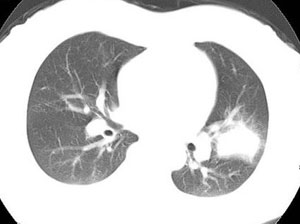

女性,30岁。

病史为胸痛20多天,无畏寒发热,无消瘦,无咳嗽咳痰。总之症状很逍遥。

临床以胸痛待查收住入院。

双肺野可见散在大小不等结节及肿块影,内密度不均匀,边缘部分清,部分欠清,纵隔未见明显肿大淋巴结.右侧胸腔少理积液.结合临床,考虑韦格肉芽肿可能吧,巨淋巴增生,结节病,特殊感染都要考虑.转移瘤临床不象.

本病例特点如下:

1.青年女性,以胸痛20多天就诊,无呼吸道及感染临床症状体征,无原发肿瘤病史;

2.肺ct表现为两肺多发大小不等结节影,大结节位于肺尖部,小结节多位于肺外带胸膜下,大结节内可见支气管充气征,周围可见月晕征(指在结节状或肉芽肿样病灶周围呈环形磨玻璃影),右肺门及腔静脉后可见小淋巴结,右侧胸腔内少量液体。

两肺散在分布大小不等的肿块及结节影,边缘毛糙,有分叶、毛刺,病灶密度不均匀,可见支气管充气相与空泡征。病变大多位于胸膜下,可见胸膜凹陷及胸腔积液。气管腔静脉间可见小结节影。